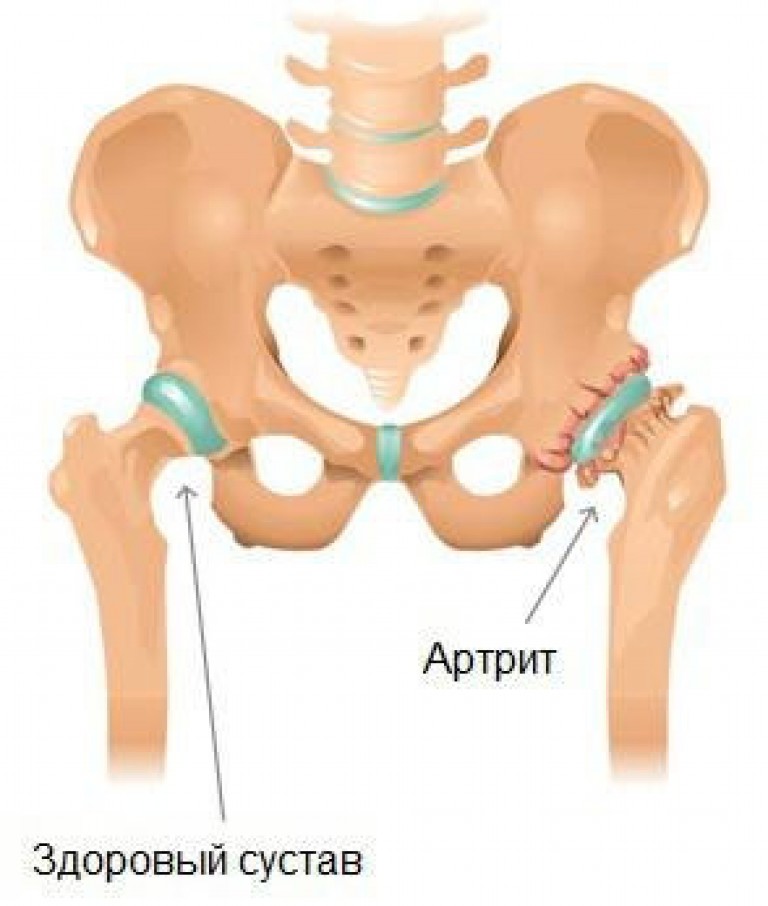

Фотографии и схемы: Коксит правого тазобедренного сустава